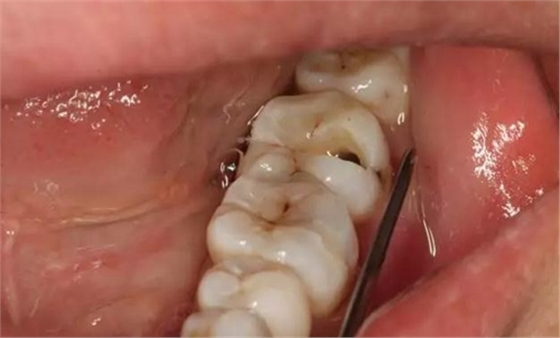

圖2. 37牙冠基本完好,松動Ⅰ度。合面有一開髓孔被棉球覆蓋,頰側(cè)牙齦輕度紅腫。

圖3. 取出棉球口內(nèi)發(fā)現(xiàn)37合面有開髓孔,探針出血,頰側(cè)牙齦紅腫。